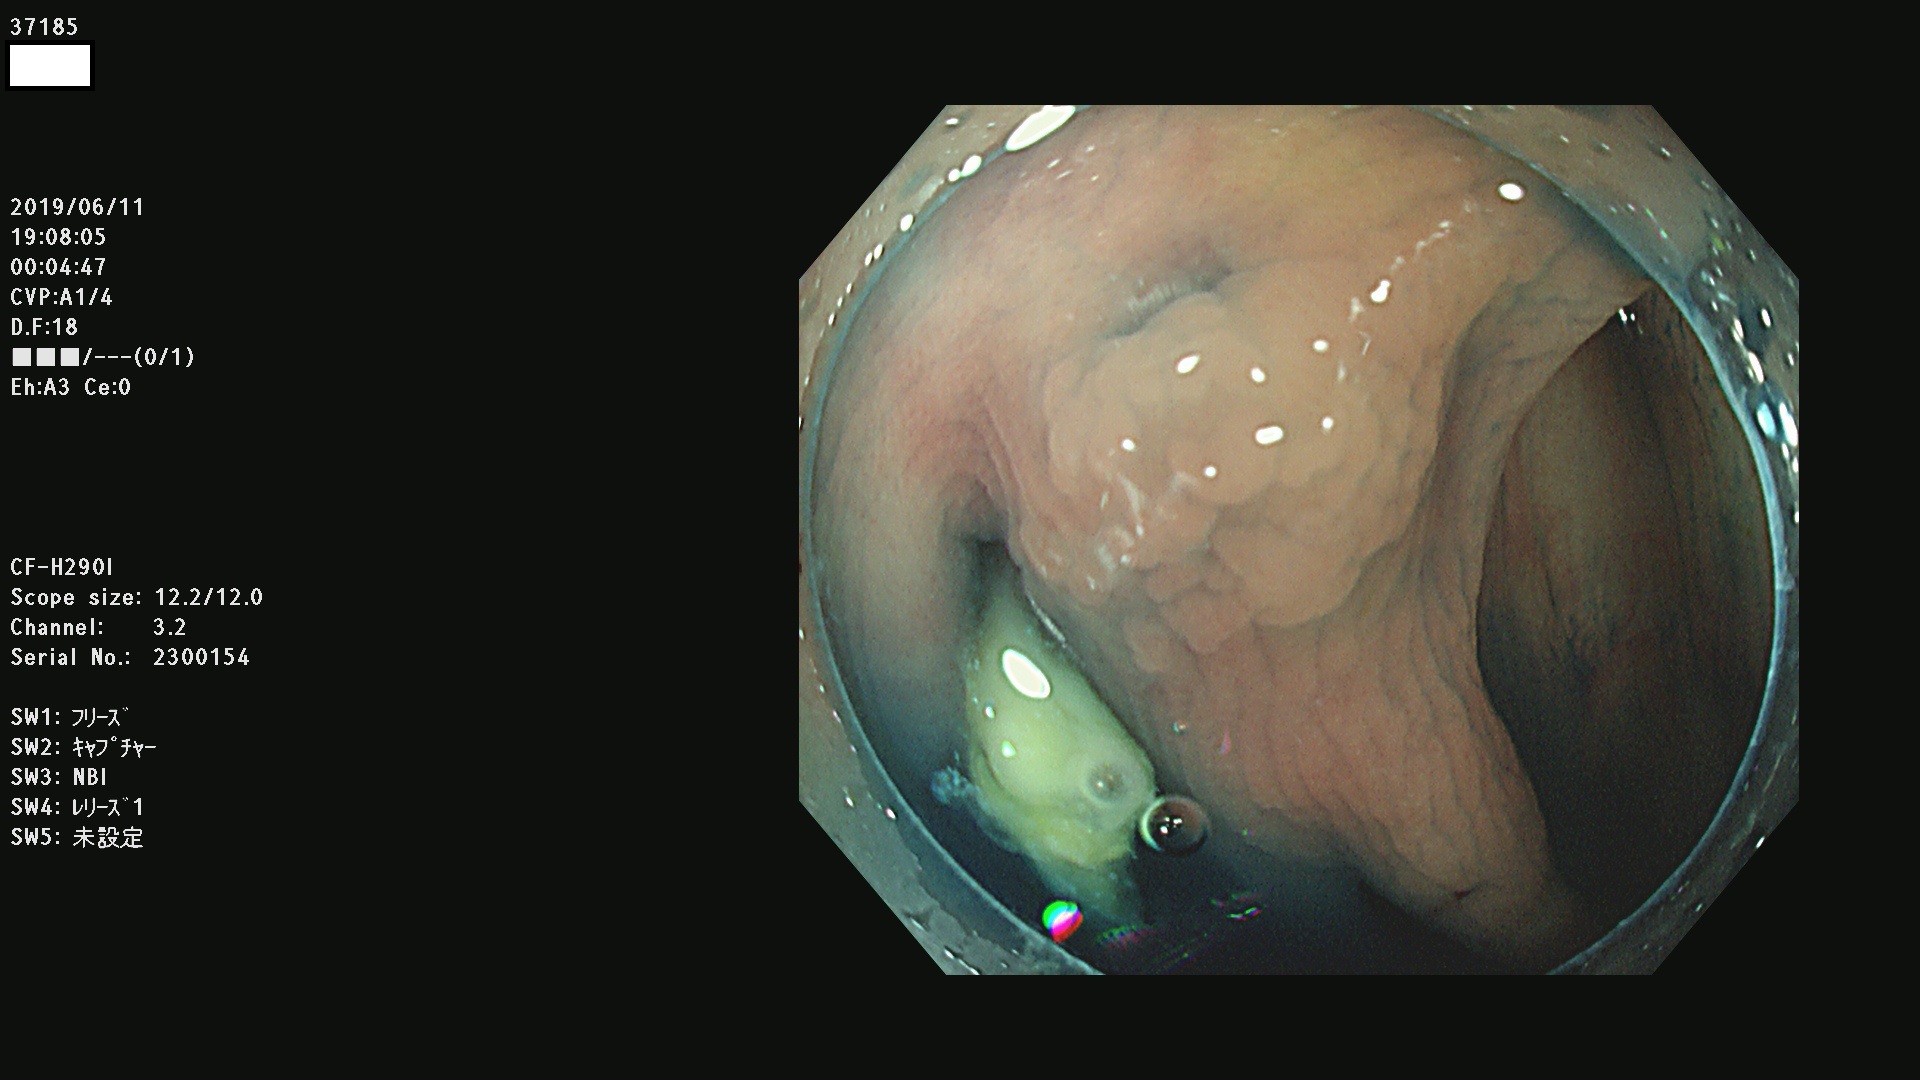

37100 37101 37102 37104 37106 37108 37110 37111 37112 37113 37115 37118(SSAPのみ) 37120 37122 37123 37124 37127(SSAPのみ) 37128(SSAPのみ) 37131 37132 37133 37134 37135 37139 37141 37142 37143 37144(SSAPのみ) 37145 37147(SSAPのみ) 37148 37149 37150 37153 37154 37157 37159 37161 37162 37163 37164 37165 37166 37167 37168 37169 37170 37171 37172 37173 37175(SSAPのみ) 37176 37177 37178 37180(SSAPのみ) 37181 37184 37185 37186 37187 37188 37189 37190 37192 37194 37197 37198

発見困難で危険性の高い平坦型病変(上記100名より抽出)